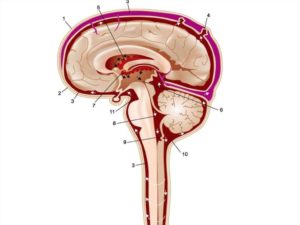

В местах, где субарахноидальное пространство естественным образом расширено, образуются мозговые цистерны, это значит, что основной объем циркулирующей цереброспинальной жидкости содержится в этих полостях. Подпаутинные цистерны – зоны естественного увеличения объема субарахноидального пространства, которые преимущественно находятся у основания мозга головы. Самые большие цистерны – базальная и затылочная.

Неравномерное расширение области субарахноидального пространства, расположенного в головном мозге, у взрослых пациентов встречается редко. Чаще патология выявляется у детей младенческого возраста. У новорожденных объем подпаутинной полости в норме меньше, чем у взрослого. Мозговые цистерны представляют собой часть сети, по которой осуществляется циркуляция цереброспинальной жидкости.

Цистерны – внешние резервуары, в то время как желудочки – внутренние. Если процессы продукции и резорбции (всасывание) ликвора уравновешивают друг друга, циркуляция поддерживается в нормальном режиме.

Размеры субарахноидального пространства в норме в 3 месяца не превышают 3 мм у доношенных младенцев, 4 мм – у недоношенных детей. Нормальные размеры мозговых цистерн составляют: большая цистерна, расположенная под мозжечком – до 10 мм (сагиттальный срез), цистерна четверохолмия – до 3 мм. Объем циркулирующего ликвора составляет около 120-140 мл.